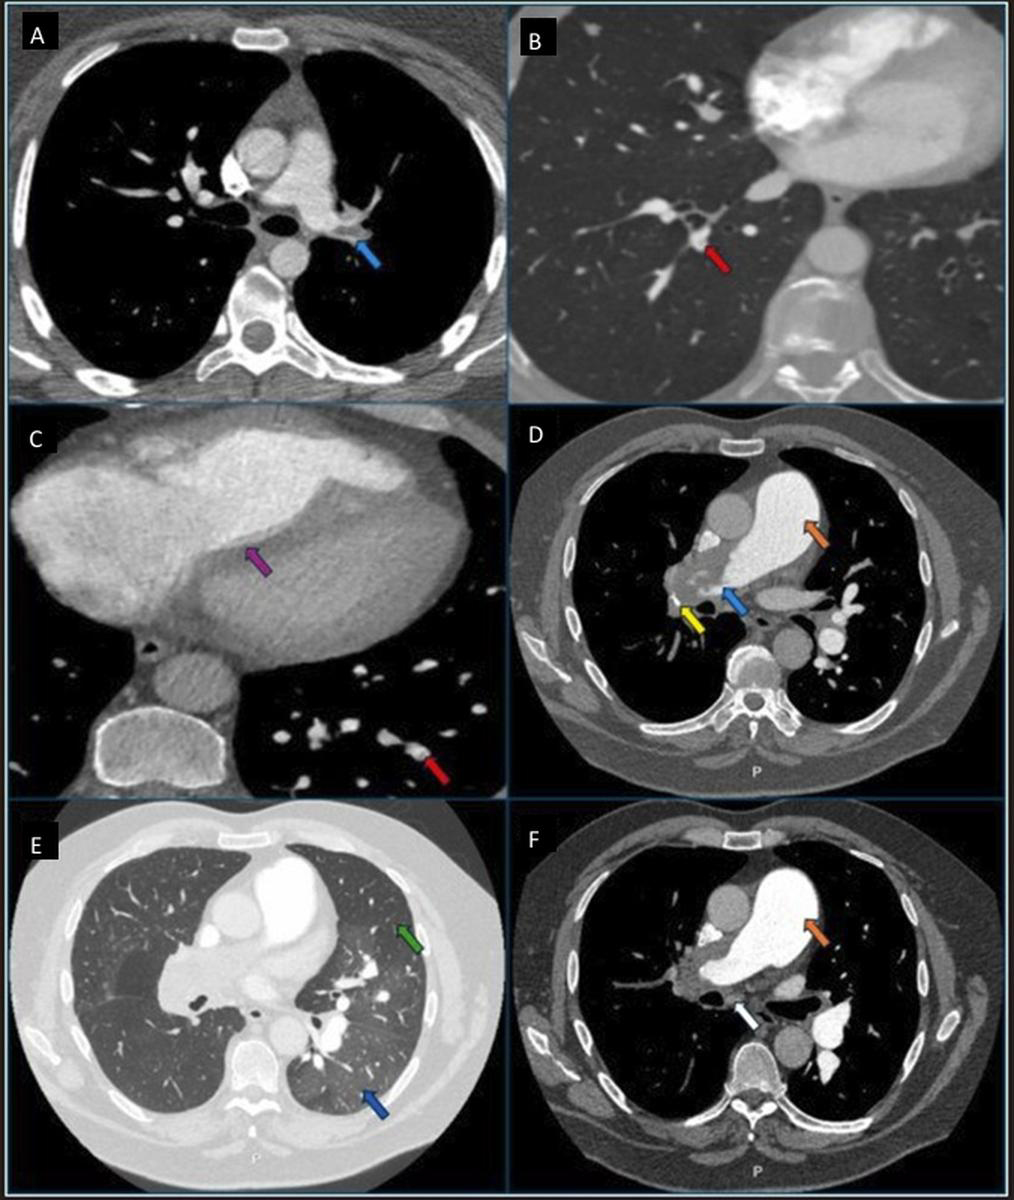

CTPA is the most readily available and widely used imaging modality to visualise the pulmonary vasculature in suspected CTEPH. CTPA identifies direct vascular features of CTEPH, including eccentric thrombus, webs, bands, calcified thrombus and pulmonary artery narrowing. Indirect vascular signs include main pulmonary artery dilatation and bronchial artery enlargement in advanced cases. Parenchymal findings may include a mosaic attenuation pattern: cardiac features suggestive of PH include right heart chamber dilatation, increased RV/left ventricle (LV) ratio, interventricular septal flattening, and hepatic venous reflux of contrast suggestive of tricuspid regurgitation [24]. Fig. 4 (Ref. [24]) shows radiological features of CTEPH on CTPA.

Fig. 4.

Chronic thromboembolic pulmonary disease (CTEPD) features on computed tomography pulmonary angiogram (CTPA). (A) CTEPD without pulmonary hypertension (PH) patient with extensive left main pulmonary artery chronic thrombi with intimal irregularity and obtuse angle (light blue arrow). Note the non-dilated main pulmonary artery. (B) CTEPD without PH patient with pulmonary artery web/band (red arrow). Note the normal right-to-left ventricle ratio. (C) CTEPH patient with dilated right heart chambers with flattening of the interventricular septum (purple arrow) and pulmonary artery web/band (red arrow). (D) CTEPH patient with calcification (yellow arrow) in extensive occluding proximal chronic thrombi, irregular intimal contour with obtuse angle (light blue arrow) and dilated main pulmonary artery (orange arrow). (E) CTEPH patient with mosaicism with areas of hypo-attenuation and vascular pruning in the region of vascular obstruction (green arrow) and normal/hyper-attenuation in the region without vascular obstruction (dark blue arrow). (F) CTEPH patient with dilated bronchial artery (white arrow) and dilated main pulmonary artery (orange arrow). Reprinted with permission from Ghani et al. [24], available under the CC BY-NC-ND 4.0 https://creativecommons.org/licenses/by-nc-nd/4.0/.

CTPA’s main advantages are its high-definition imaging, short scan duration, and ability to detect both vascular obstruction and secondary cardiac changes. The main limitation includes the requirement of iodinated contrast, making it unsuitable for some patients with severe renal impairment or contrast allergy, and the inability to provide direct lung perfusion assessment. In addition, subtle or distal chronic thrombi may be missed without expert interpretation, with a specificity of 25% in diagnosing sub-segmental lesions in some studies [25].

Despite these limitations, advances in computed tomography (CT) technology and radiologist expertise have significantly improved its diagnostic accuracy, with reported sensitivity of 88%–98% and specificity of 89%–96% [24, 25].